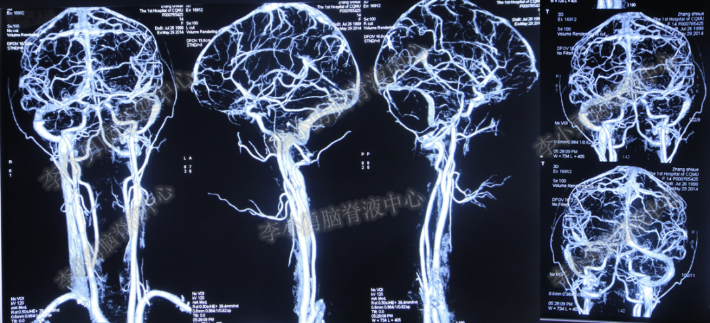

患者因恶心、呕吐伴头痛头晕,自行服药后无法自行缓解,于2014年5月29日就诊位于重庆的著名的三甲肿瘤医院,查全脑CTA和CT后诊断为“小脑蚓部占位伴幕上脑积水”(图-1、图-2)。

图-1:2014年5月29日全脑CTA